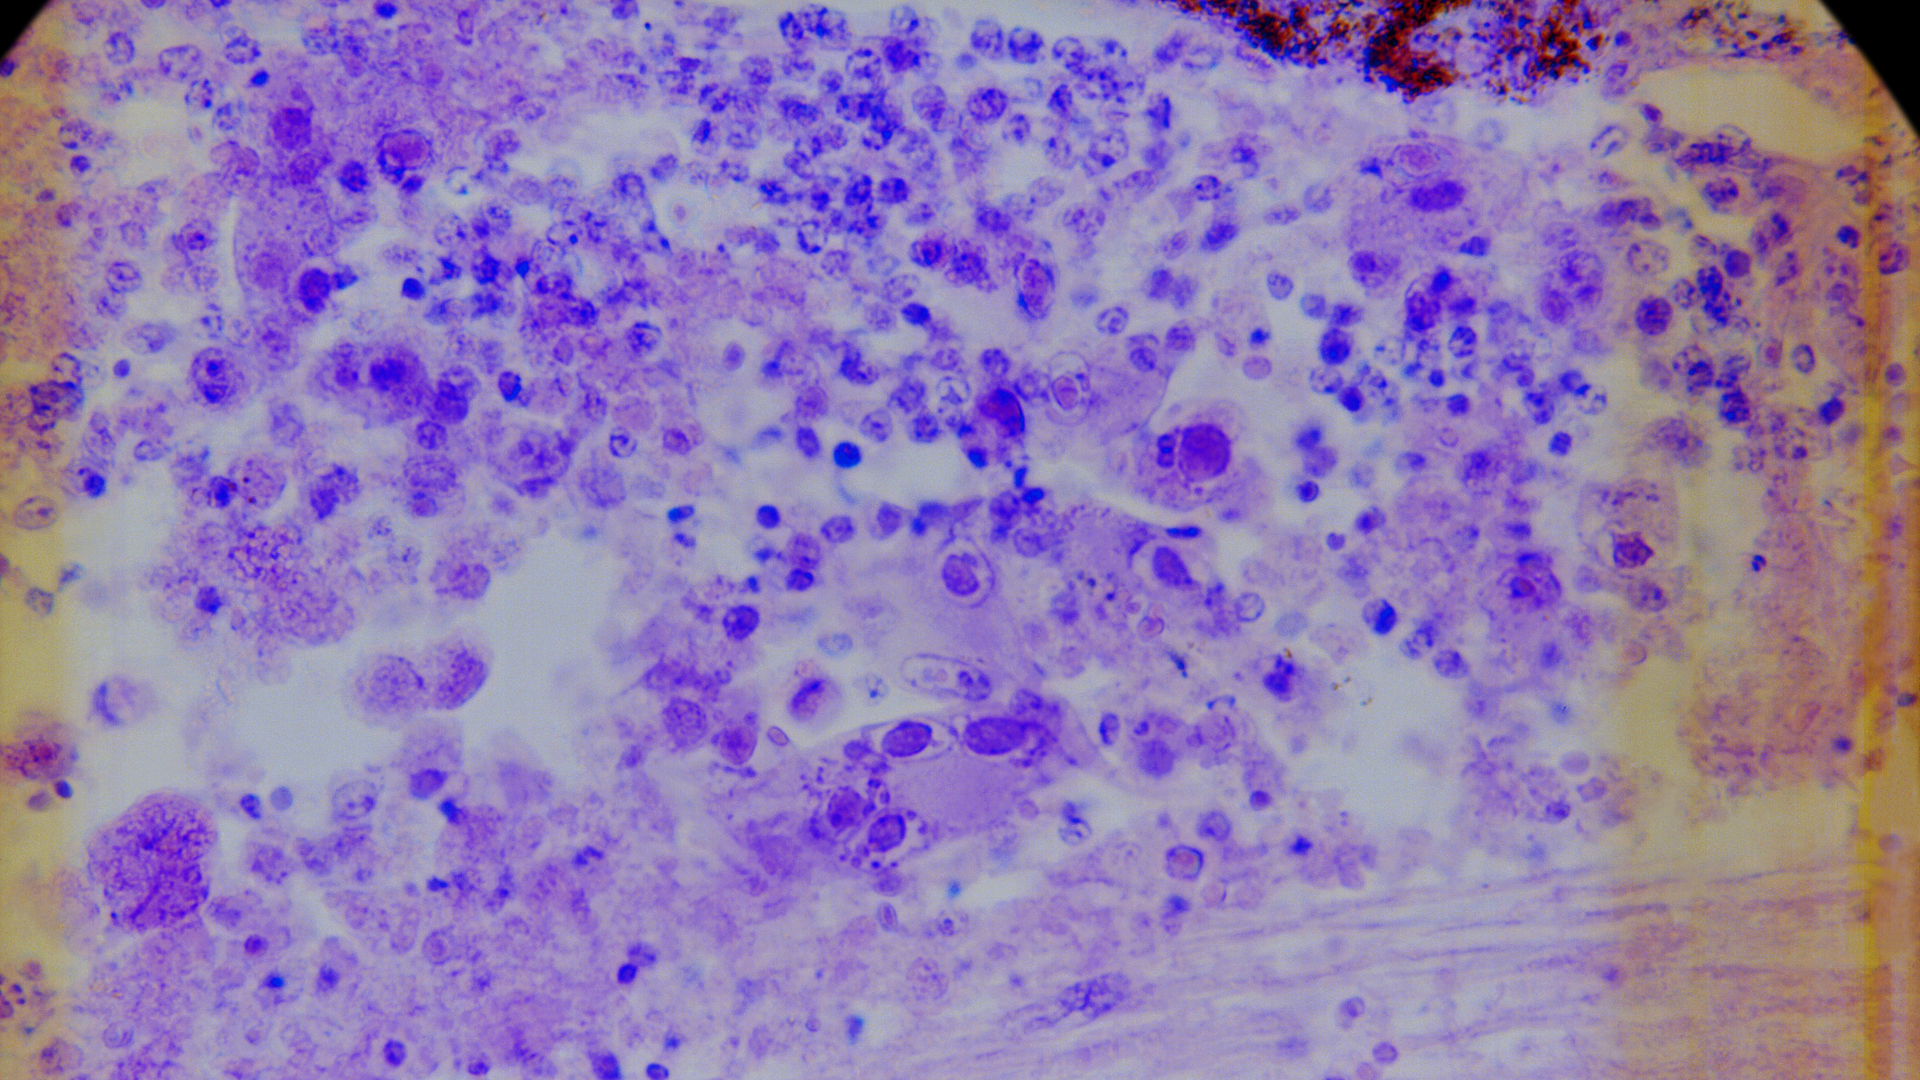

ZUMA-7 is a nationwide, multicenter phase 3 trial evaluating Yescarta as a second-line therapy for patients with diffuse large B-cell lymphoma. In total, 359 patients were enrolled and randomized into two arms: Yescarta or standard of care. Patients in the Yescarta arm underwent apheresis to have CAR T cells produced for therapy. Those in the standard of care arm were given chemotherapy with the goal of getting them well enough for an autologous stem cell transplant.

Large B-cell lymphoma is the most common type of non-Hodgkin lymphoma. Roughly 40% of patients will relapse and require a second-line therapy. Locke says providing CAR T as an option sooner for this patient population can reduce exposure to toxic chemotherapy agents and provide better outcomes and a quicker recovery.